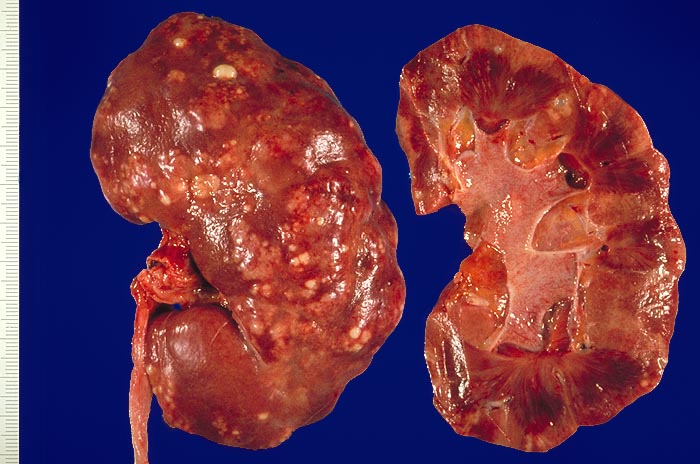

PathoPic – image database / PathoPic ID 1747 - Akute Pyelonephritis

Akute Pyelonephritis

Schwerste akute Pyelonephritis. An der Nierenoberfläche erkennt man zahllose gelbe, leicht erhabene Herde, die von einem zarten roten Randsaum umgeben sind. Daneben bestehen kleinere Narbenfelder mit Einziehung der Niererinde. Auf der Schnittfläche sieht man Eiterstrassen, welche das Parenchym von der Papille bis zur Rinde durchziehen. Rötung der Nierenbeckenschleimhaut (Pyelitis).